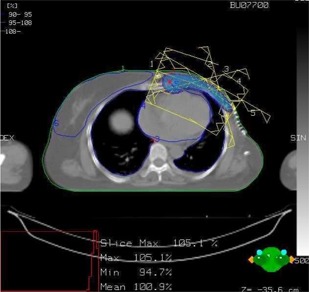

Figure 1 shows the isodose distribution in the axial plane for IMCBT and 3DCRT in PLATO EVAL module. The contribution from both the external and brachytherapy is displayed. Internal mammary chain was the target for brachytherapy, while the left breast was the target for external. Internal mammary chain was treated with HDR, while the left breast was treated with two parallel‐opposed conformal tangential 6‐MV photon beams with 15° wedges. Figure 2 shows the integral DVH for heart, lungs, coronary, and left IMC for IMCBT and 3DCRT with PLATO. Figure 3 shows the integral DVH for PTV and IMC for IMCBT and 3DCRT with PLATO. Internal mammary chain, as well as the left breast, was covered with the 95% isodose. Figure 4 shows the isodose distribution in the axial plane for IMRT in Cadplan. The isodose washes of 90%, 95%, and 108% are shown. The PTV here was the IMC included in the left breast. Five coplanar beams were placed with 6‐MV photons. Figure 5 shows the DVH for PTV, heart and both lungs for IMRT in Cadplan.

Figure 4.

The isodose distribution in axial plane for IMRT with Cadplan. The typical IMRT plan shows five coplanar 6‐MV photon beams. The PTV includes left breast and IMC. The distribution shows 95% to 108% isodose lines around the PTV.